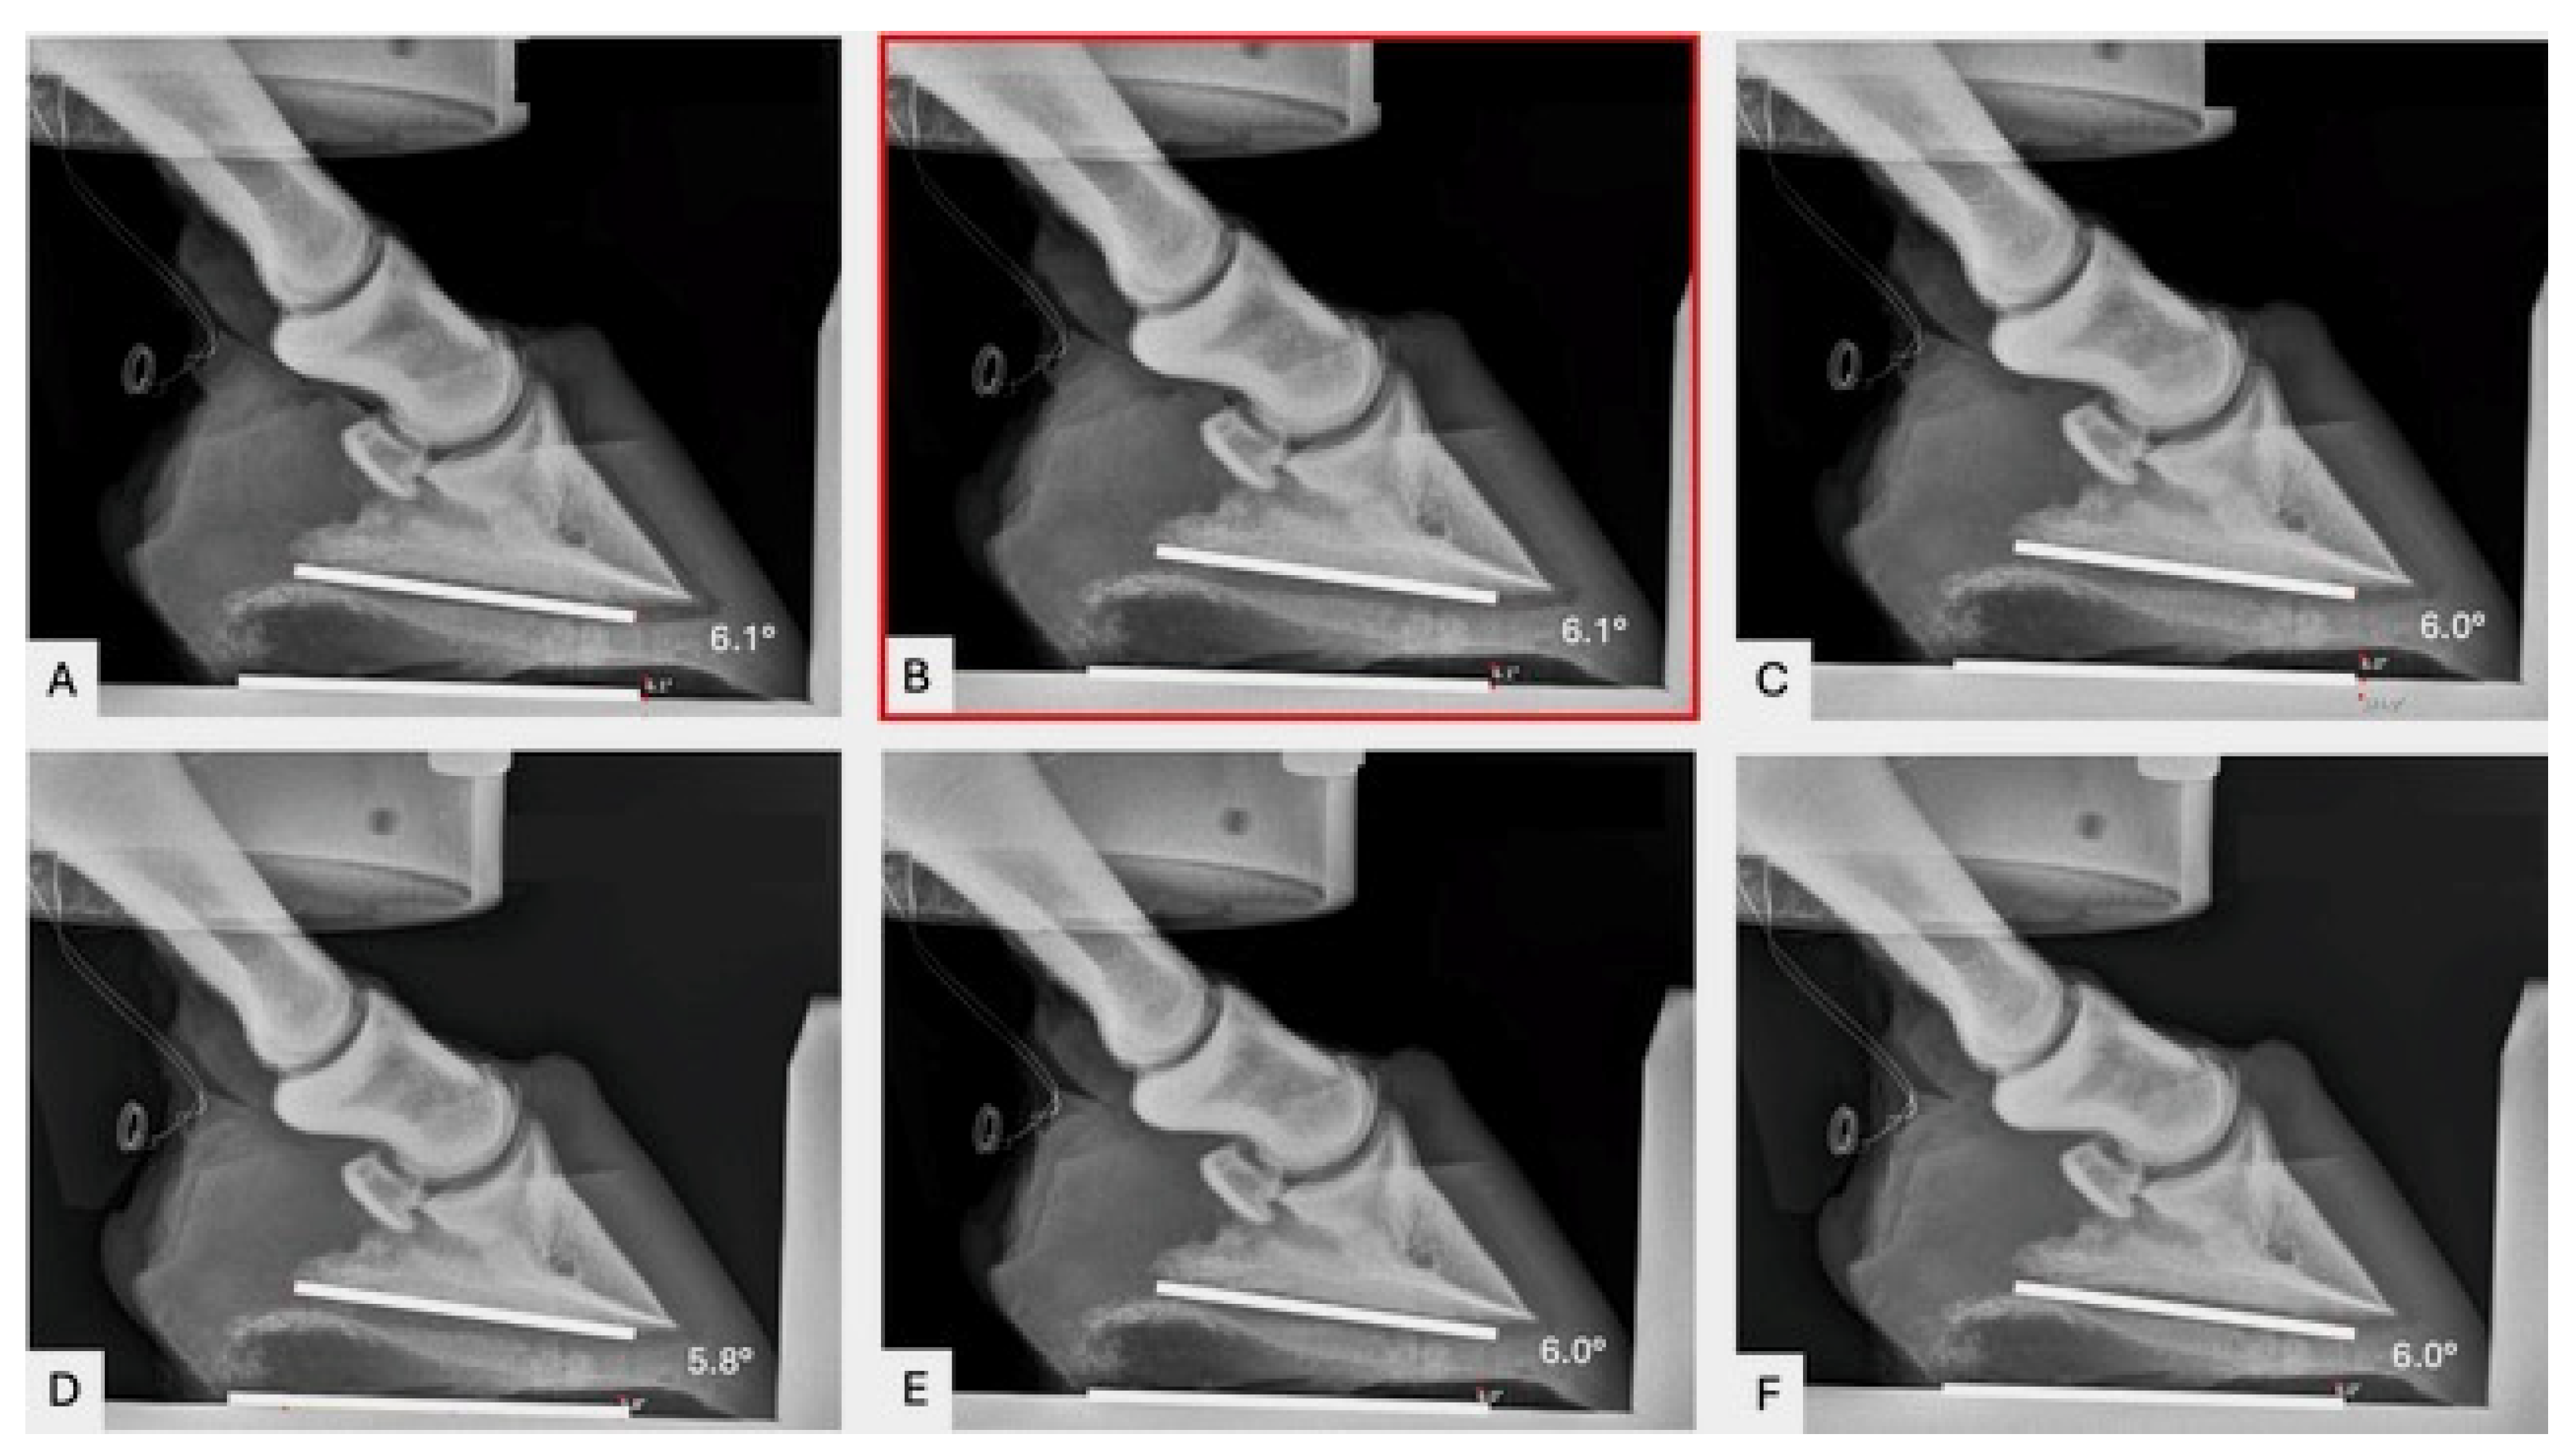

2.2. Radiography

For all hoof specimens, lateromedial radiographs (80 KvP, mAs 0.8) were obtained with the X-ray beam centered at the hoof–ground interface [20], using a portable digital X-ray machine. This was performed after the limbs were secured in the mechanical testing system (MTS) and loaded to 100 N. Lateromedial radiographic views were repeated throughout the course of the study for every loading scenario and every wedge scenario. The PA was measured (Antech Imaging Services, Dark Horse Medical Ventures, Irvine, CA, USA) on the lateromedial radiographs by placing a line along the base of P3 and measuring the angle at which it intersected with a line parallel with the ground/platform (Figure 1).

Figure 1. Serial radiographs of a left front foot. PA (lower right value) was measured using the radiographic imaging platform. White lines were placed on figures for visualization. (A) 100 newtons (N), (B) 1000N, (C) 2000N, (D) 3000N, (E) 4000N, and (F) 5000N. The neutral PA was measured under 1000 N of load (B, red box). Dorsal is to the right. Palmar is to the left. The wires visible on the left of the radiographs are the identification tags.